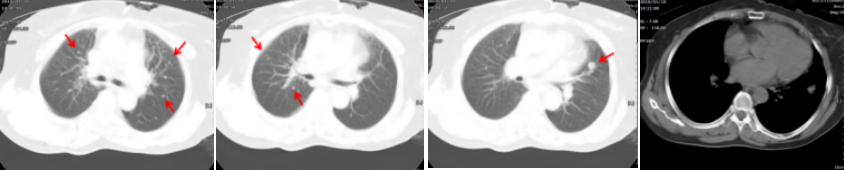

病例简介 该病例是一个肺腺癌(cT4N0M1a)IVa期患者,合并有高血压、冠心病、糖尿病。一线治疗前基因检测结果提示EGFR 19del(+)。一线治疗(埃克替尼片125mg tid)疗效评估为PR、PFS 22个月。一线治疗前基因检测结果提示EGFR 19Del(+)、T790M(+)。后入组D0316(贝福替尼)在EGFR阳性局部晚期或转移性非小细胞肺癌的II期临床试验(IBIO-102项目)。治疗先后由D0316 75mg qd更改方案为D0316 100mg qd,疗效评估为PR,、PFS>32月。至今患者仍持续用药随访中。 Part 1 基本信息 患者:女性;74岁。 主述:反复咳嗽3年,加重伴呼吸费力4月,于2018-1-17就诊。 既往史: 高血压病史10年,服用络活喜、厄贝沙坦氢氯噻嗪、美托洛尔控制血压;冠心病,冠脉支架置入术后4年;糖尿病史2年;否认其他病史。 Part 2 诊疗经过 治疗前辅助检查 2018-1-17查体:血压129/85mmHg;无明显阳性体征。 实验室检查 2018-1-18:血CEA 9.9ng/ml、Cyfra21-1 4.3ng/ml;SCC、NSE、Pro-grp均正常;血常规(Hb 109g/l)、肝肾功能、crp正常。 影像学检查 2018-1-8胸部CT:两肺多发结节,考虑MT伴转移,对照2017-10-4片增大,冠脉钙化,左侧部分肋骨陈旧性骨折,胆囊结石; 2018-1-22腹部B超:脂肪肝倾向,胆囊结石,两肾囊肿,两侧肾上腺未见明显异常回声; 2018-1-21头颅MRI:平扫+增强未见明显异常; 2018-1-23骨ECT:全身骨显像未见明显转移征象。 治疗前病理诊断 肺腺癌(cT4N0M1a) IVa期; 2018-1-18肺穿刺及病理:CK7( ++++ );NapsinA( ++++ ) ;TIF-1(++++);EGFR 19Del(+) ;ALK(-) 。 治疗前临床诊断 肺腺癌(cT4N0M1a) IVa期;PS 1分;EGFR 19Del(+);冠心病、冠脉支架置入术后;高血压病;糖尿病。 一线治疗 治疗方案:2018-1-26开始,埃克替尼片125mg tid。 疗效评估(PR,PFS 22月 ) 埃克替尼治疗11.3个月,两肺结节减少、缩小,达到PR (2018-12-4);治疗22个月,左下肺结节增大、肺内新发小结节、新发心包积液,出现PD(2019-11-21)。 2018-1-18 治疗前基线 2018-12-4 埃克替尼 11.3月(PR) 2019-11-21 埃克替尼 22月(PD) 一线治疗后辅助检查 实验室检查 2019-11-29血CEA 8.4ng/ml ;Cyfra21-1 4.8ng/ml;SCC、NSE、Pro-grp均正常。 2019-12-13血生化肌酐84umol/l;肝功能正常;血常规正常。 影像学检查 2019-12-4头颅MRI平扫+增强:脑内少许腔梗灶; 2019-12-2骨ECT:全身骨显像未见明显转移征象; 2019-12-4腹部增强CT:胆囊结石,右肾上腺及胰腺钙化灶,两肾囊肿。 生理学检查 2019-12-13 ECG:窦性心律,T波改变; 2019-12-13心超:左室轻度增大,左室壁偏厚,左房轻度增大,轻度肺动脉高压伴轻度三尖瓣返流,心包积液,脏层心包增厚,左室舒张功能轻度减退。 一线治疗后病理诊断 2019-11-29分子病理(ARMS法):EGFR 19Del(+) ;T790M(+)。 临床诊断 肺腺癌(cT4N0M1a);IVa期;肺、心包转移;PS 1分;EGFR 19Del(+);T790M(+);冠心病;冠脉支架置入术后;高血压病;糖尿病;肾功能不全。 二线治疗 入组D0316(贝福替尼)在EGFR阳性局部晚期或转移性非小细胞肺癌的II期临床试验(IBIO-102项目)。 治疗方案 2019-12-19开始D0316 75mg qd,于2019-12-24至2020-1-15出现头痛、肩背痛1级AE,自行缓解; 2020-1-13开始D0316 100mg qd; 合并用药有针对糖尿病药物西格列汀片 50mg qd;针对高血压药物氨氯地平5mg qd、厄贝沙坦氢氯噻嗪片1片qd、美托洛尔缓释片47.5mg qd;针对冠心病药物西洛他唑 50mg bid;针对睡眠障碍药物氯硝西泮片1mg qn、艾司酉酞普兰片10mg qd、喹硫平片50mg qd。 安全性评估 疗效评估(PR, PFS>32月 ) D0316 治疗6周就达到PR,患者左下肺靶病灶缩小,两肺小结节稳定、部分缩小(2020-1-28);治疗30周仍为PR,且心包积液减少(2020-7-13);治疗30.5月仍为PR,右下叶背段胸膜下结节缓慢进展(2022-6-30)。 2019-11-21 D0316 治疗前基线 2020-1-28 D0316 治疗6周(PR) 2020-7-13 D0316 治疗30周(PR) 2022-6-30 D0316 治疗30.5月(PR) 2022-6-30腹部增强CT:胆囊结石,右肾上腺及胰腺钙化灶,两肾囊肿。 目前D0316(贝福替尼) 100mg qd 治疗中, PS 1分。